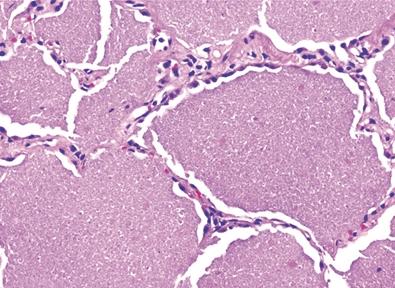

肺气肿加重时出现桶状胸,呼吸运动减弱,呼气延长,语颤音减弱或消失,叩诊呈过清音,心浊音界缩小或消失,肝浊音界下降,心音遥远,呼吸音减弱,肺部有湿啰音。

2、肺大泡破裂后引起自发性气胸,并可导致大面积肺萎陷。